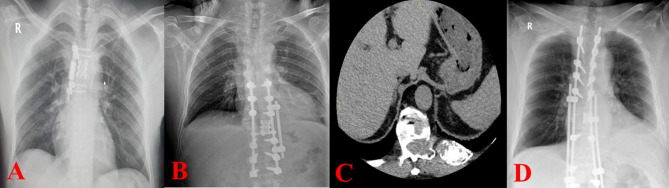

Methods: We have seen a total of 35 cases in our investigation. When doing vertebral body tethering (VBT) in chosen scoliosis patients, thoracoscopy and thoracotomy have been the favored methods. On the other hand, alternative circumstances have favored the usual thoracotomy method.

Results: We operated on three (8.6%) patients for trauma, six (17.1%) for mass, and 26 (74.2%) for scoliosis. Twenty (57.1%) of the patients operated for scoliosis underwent VBT. In patients undergoing VBT, a greater number of vertebrae were accessed thoracoscopy compared to thoracotomy (p = 0.003). There was no significant difference between the two groups in terms of chest tube follow-up time, length of stay in the intensive care unit, and hospital stay (p = 0.451, p = 0.403, p = 0.125).

Conclusion: Our investigation demonstrated that the thoracoscopy is capable of intervening with a greater number of vertebrae compared to thoracotomy. Thoracic surgeons primarily focus their research on masses and trauma related to spinal surgery. Our study's large patient population with scoliosis surgery adds to the existing body of knowledge in the field of thoracic surgery. This study is significant as it is the second in the existing literature to document the experiences of thoracic surgeons from Turkey use of VBT.